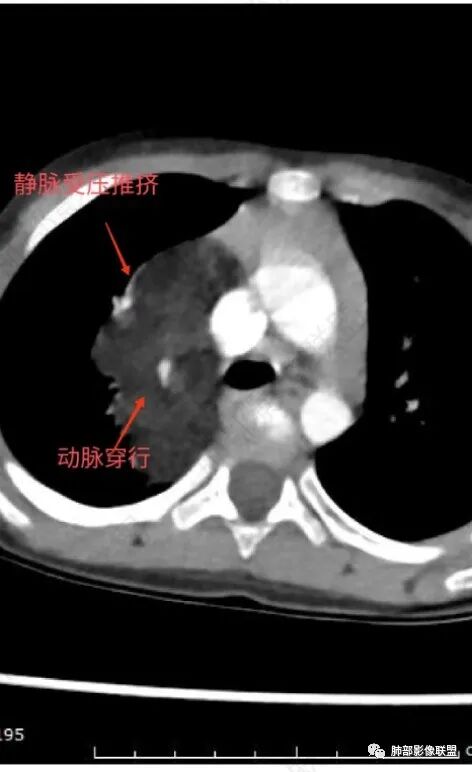

定位:肺内?尖段气管未见明显显示,腔静脉受压向右推移?病灶内可见前段动脉穿行,脂肪密度为主。

肿块起源于右上气管分叉处?强化动脉血管最后汇入右肺动脉上干。

右侧纵隔奇静脉水平起源?压迫上肺,包绕动脉?

病灶属于交界区,主体位于肺内,占位效应明显,前方突入胸壁,胸腺受压变形,胸膜显示欠清楚;病灶包绕上叶肺动脉;似乎有体动脉供血。符合肺内的点:包绕上叶肺动脉分支;符合纵隔的点:前方似乎突入胸壁,与胸腺关系比较密切,但是与上腔静脉的关系提示病灶不支持纵隔来源,前纵隔的常规会将上腔静脉受压后移、外移,这是不符合的。

2.肺动脉穿行也许是肺内来源最重要支持点!